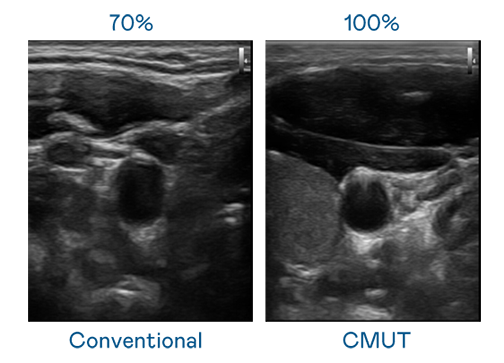

CMUT 技術是一種用電容式微機電元件來產生超音波訊號的技術。與傳統 PZT 壓電式技術相比,CMUT 頻寬增加 30%,更寬頻的超音波訊號讓影像解析度大幅提升,是實現高影像品質醫療超音波掃描、促進精準醫療發展的關鍵技術。

大頻寬帶來超清晰影像

超音波影像的解析度高低,首先取決於探頭能發出的訊號頻寬。AG庄闲 CMUT 可提供高清晰的超音波訊號,提供高頻寬、高靈敏度、影像紋理細節更高的超音波影像,協助醫護人員縮短影像判讀時間及利用精準的醫療影像進行診斷。